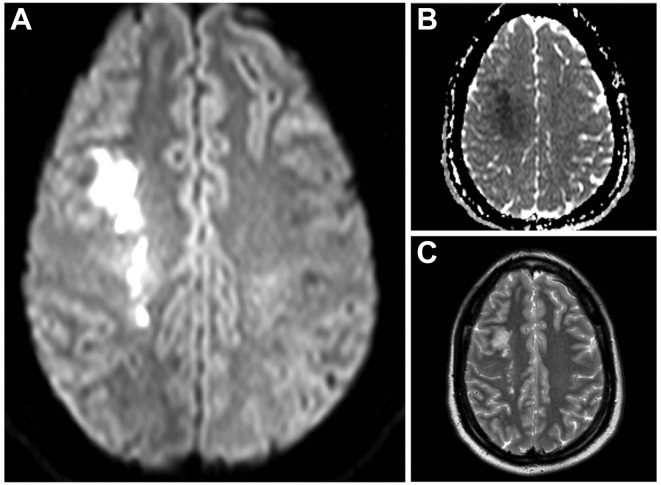

「烟雾病概述」烟雾病是什么?烟雾病(MMD)是一种脑血管结构异常,烟雾是指在脑血管造影上出现的异常血管络脉,这些络脉毗邻狭窄的血管。烟雾的狭窄侵入区通常是双侧的,但单侧的...

烟雾病的早期症状和诊断标准,烟雾病是一种进展性闭塞性脑血管病,以双侧颈内动脉末端分叉处狭窄、大脑前、中动脉异常、广泛侧支血管(烟雾血管)发育为特征。一般来说,儿童烟雾...

烟雾病是什么病?早期症状有哪些?烟雾病的特征是在大脑底部有细小的烟雾血管,导致大脑中动脉远端和/或MCAs主干发生进行性闭塞。烟雾病的特征性临床表现已被报道,包括由于脑缺...